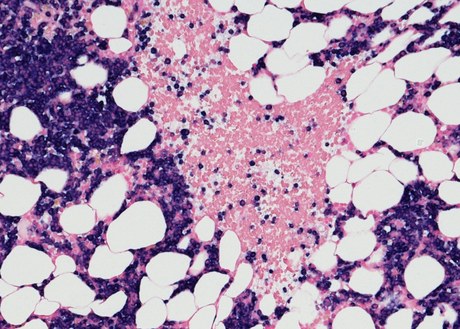

An image of chronic lymphocytic leukemia cells under a microscope